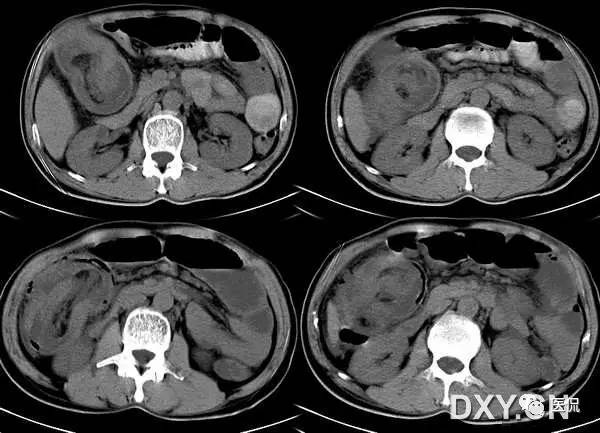

21 靶征(肠套叠)

是肠套叠最常见的特征性CT征像,为肠套叠长轴与CT扫描层面垂直时的表现,反映了套叠的各层肠壁、肠腔及肠系膜间的关系。典型排列为自外向内分别代表鞘部外层肠壁、鞘部肠腔内造影剂、鞘部内层肠壁、偏心性套入部肠系膜、套入部肠壁、套入部肠腔内造影剂。:

肠套叠是指一段肠管及与其相连的肠系膜(套入部)被套如其相连的一段长管内(鞘部),导致肠内容物通过阻碍。婴儿由于大肠与小肠管径之比例相差大。故小肠易陷入大肠而被套牢。少数肠套叠可能来自某些器质性病变如美凯尔憩室、肠息肉、异位胰腺小结、血管瘤、异物、复制肠管、淋巴增生、肿瘤、寄生虫等,其中以美凯尔憩室最多,过敏性紫斑也常会合并肠套叠,大于2岁的小孩发生肠套叠,一定要考虑到这些病变。大于5岁的病例中,则以淋巴瘤为最多;成人肠套叠小肠多见,常伴发良性病变;结肠型肠套叠则更多由恶性病变继发。良性病变有脂肪瘤、平滑肌瘤、血管瘤、神经纤维瘤、腺瘤样息肉、美克尔憩室、术后粘连机场动力性病变等;恶性病变有转移瘤、腺癌、类癌、淋巴瘤及平滑肌肉瘤等。由于肠套叠长轴与CT扫描层面的角度不同,表现各异。如扫描层面和迂曲的肠道相平行时,表现为彗星尾征或肾形征:即套叠近端肠系膜血管牵拉聚拢的征象。一般情况下,慧星尾征均与肾型肿块相伴出现。该肾形肿块为套鞘部游离缘与套入部近端肠管及肠系膜的CT斜切面图像,其中游离的套鞘呈弧形围绕套入部,形状若肾轮廓外形,而套入部近端肠管、肠系膜形状若肾蒂。此时,所谓慧星尾征的组成还应包括套入近端肠管。如果套叠的肠管与CT扫描垂直,则呈靶形征,即肿块影表现为圆形或类似环形。通常在肿块内可分辨出层样结构,推测可能是继发于套入部和鞘部间的液体或是肠壁水肿造成密度对比,类似同心圆形;当套入部肠壁显著水肿坏死或套入部肿瘤周围浸润累及肠系膜,肠系膜血管及脂肪、套叠时间较长,套入部系膜血管受挤压时,静脉血液回流障碍,套入部肠壁充血水肿、变硬,形成不完全性肠梗阻,套叠以上肠管蠕动增强,可引起代偿性肠管扩张肥厚,并可见肠系膜连同其血管纠集、扭曲,形成“漩涡征”。

成人肠套叠还有一些间接征象可帮助诊断,如肠壁不规则增厚或见密度不均匀的软组织块影,伴周围系膜及筋膜浸润、腹膜后淋巴结增大,则提示病因是恶性肿瘤。肿瘤所致肠壁水肿、坏死与部分炎症引起的套叠无法明确区分,肠壁及肠系膜血管有增厚伴肠壁内气体影的征象可提示血运障碍。如CT显示肠套叠直接征象、并伴随近段肠梗阻征象,则表示套入时间较长。如果套入部肠壁及鞘部组织发生水肿、变硬,形成不完全性肠梗阻,套叠以上肠管蠕动增强,可引起代偿性肠管扩张肥厚。

肠套叠形成的“靶征”

扫描层面和迂曲的肠道相平行时,表现为彗星尾征或肾形征:即套叠近端肠系膜血管牵拉聚拢的征象。

22 靶征(肠壁)

主要见于腹部增强扫描,增后的肠壁表现为三层结构,内层和外层是高密度强化层,两者之间是低密度的中间层。

靶征出现于可导致长鼻粘膜水肿、炎症或两者同时存在的多种肠管病变。其内层代表粘膜层,外层代表固有层和浆膜层,由于对比剂的强化而成高密度,中层的低密度被认为是由于粘膜下层水肿所致。靶征的出现提示粘膜和固有层、浆膜层的充血并伴有粘膜下水肿和炎症。颈静脉注射对比剂后,各层之间的密度差异在动脉早期和门晚期表现最为清楚,如果对比剂注入速度太慢、剂量太少以及延时超过2分钟,此征根本不出现。但是当粘膜下水肿非常严重时,CT平扫也可能出现。如果肠管内充满水而使肠管扩张时,靶征显示更为清楚。

CT扫描时,良性的肠管病变通常表现为肠壁的环形均匀性增厚,厚度从粘膜面到浆膜面一般不超过1公分,根据病因和病变严重程度的不同,偶尔可能超过1公分,但一般在2公分以内。肠壁出现靶征的病变主要见于缺血性肠病、小肠壁内出血、克隆氏病、溃疡性结肠炎、血管性疾病、感染性疾病、放射疾病和门脉高压所致肠粘膜水肿等。靶征并不是一个特异征象,但是在恶性病变中一般不出现此征,只是浸润性直肠癌是一个例外。

所以,一般情况下,靶征的出现,首先要考虑的是肠道的炎症性病变。以下病例是一个系统性红斑狼疮的年轻女性患者: